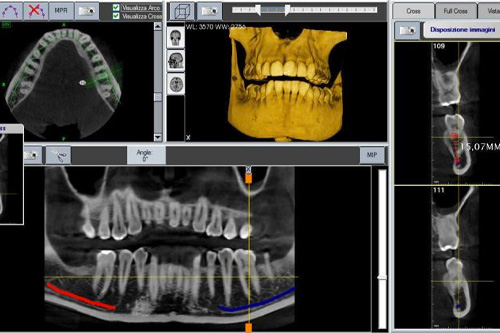

The implant placement position is essential in determining the success of a surgical implant. In order to place the implant in a precise location surrounded by adequate bone and away from vital structures such as nerves and vessels, SmileBay combines 3D x-ray imaging from our CBCT machines with the intra-oral digital scans from our 3Shape TRIOS in an implant planning software. Our dentists can then plan the most ideal implant position pre- surgery, and 3D print surgical templates to guide the implant into the pre-planned position during surgery.

CBCT imaging provides detailed 3D images of the oral and maxillofacial regions. This technology allows dentists to visualise complex anatomical structures and accurately assess conditions such as impacted teeth, jawbone density, and temporomandibular joint disorders. CBCT scans aid in precise treatment planning for dental implants, orthodontics, and oral surgeries, leading to improved outcomes and reduced risk. SmileBay uses high-end CBCT machines such as the Vatech Green16, PaX-i3D Smart, which emphasises patients’ comfort and safety with its small and user-friendly footprint, low dosage radiography and rapid <10 second scan time!